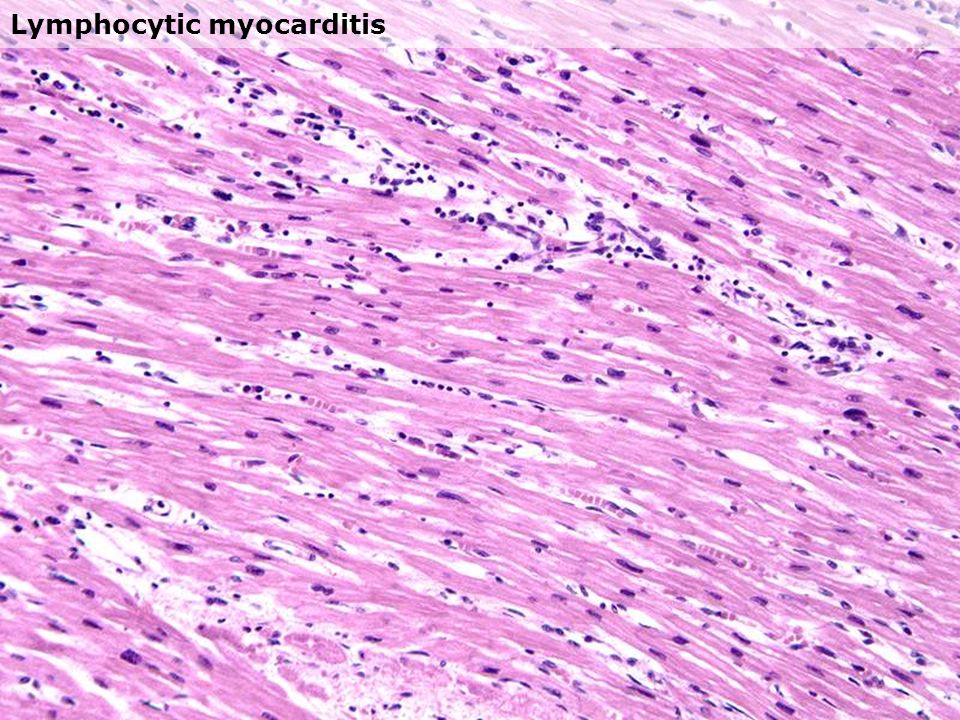

Межуточный миокардит: гистологические исследования

Раздел: Идеи и советы